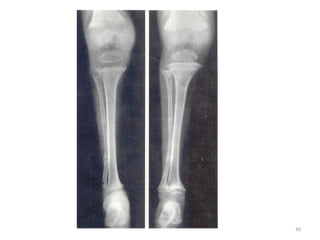

SIGNES METAPHYSAIRES

- Elargissement des bases métaphysaires avec aspect en cupule ou « toit de

pagode »

- Elargissement des zones radio-transparentes (points d’ossification)

ATTEINTES EPIPHYSAIRES

- Retard d’apparition des points d’ossification

- Points d’ossification flous ou irréguliers

LESIONS DIAPHYSAIRES

- Diminution de la densité osseuse

- Amincissement des corticales

- Aspect de corticale feuilletée

- Coxa vara, genu varum

- Pseudo-fracture de Looser- Milkmann